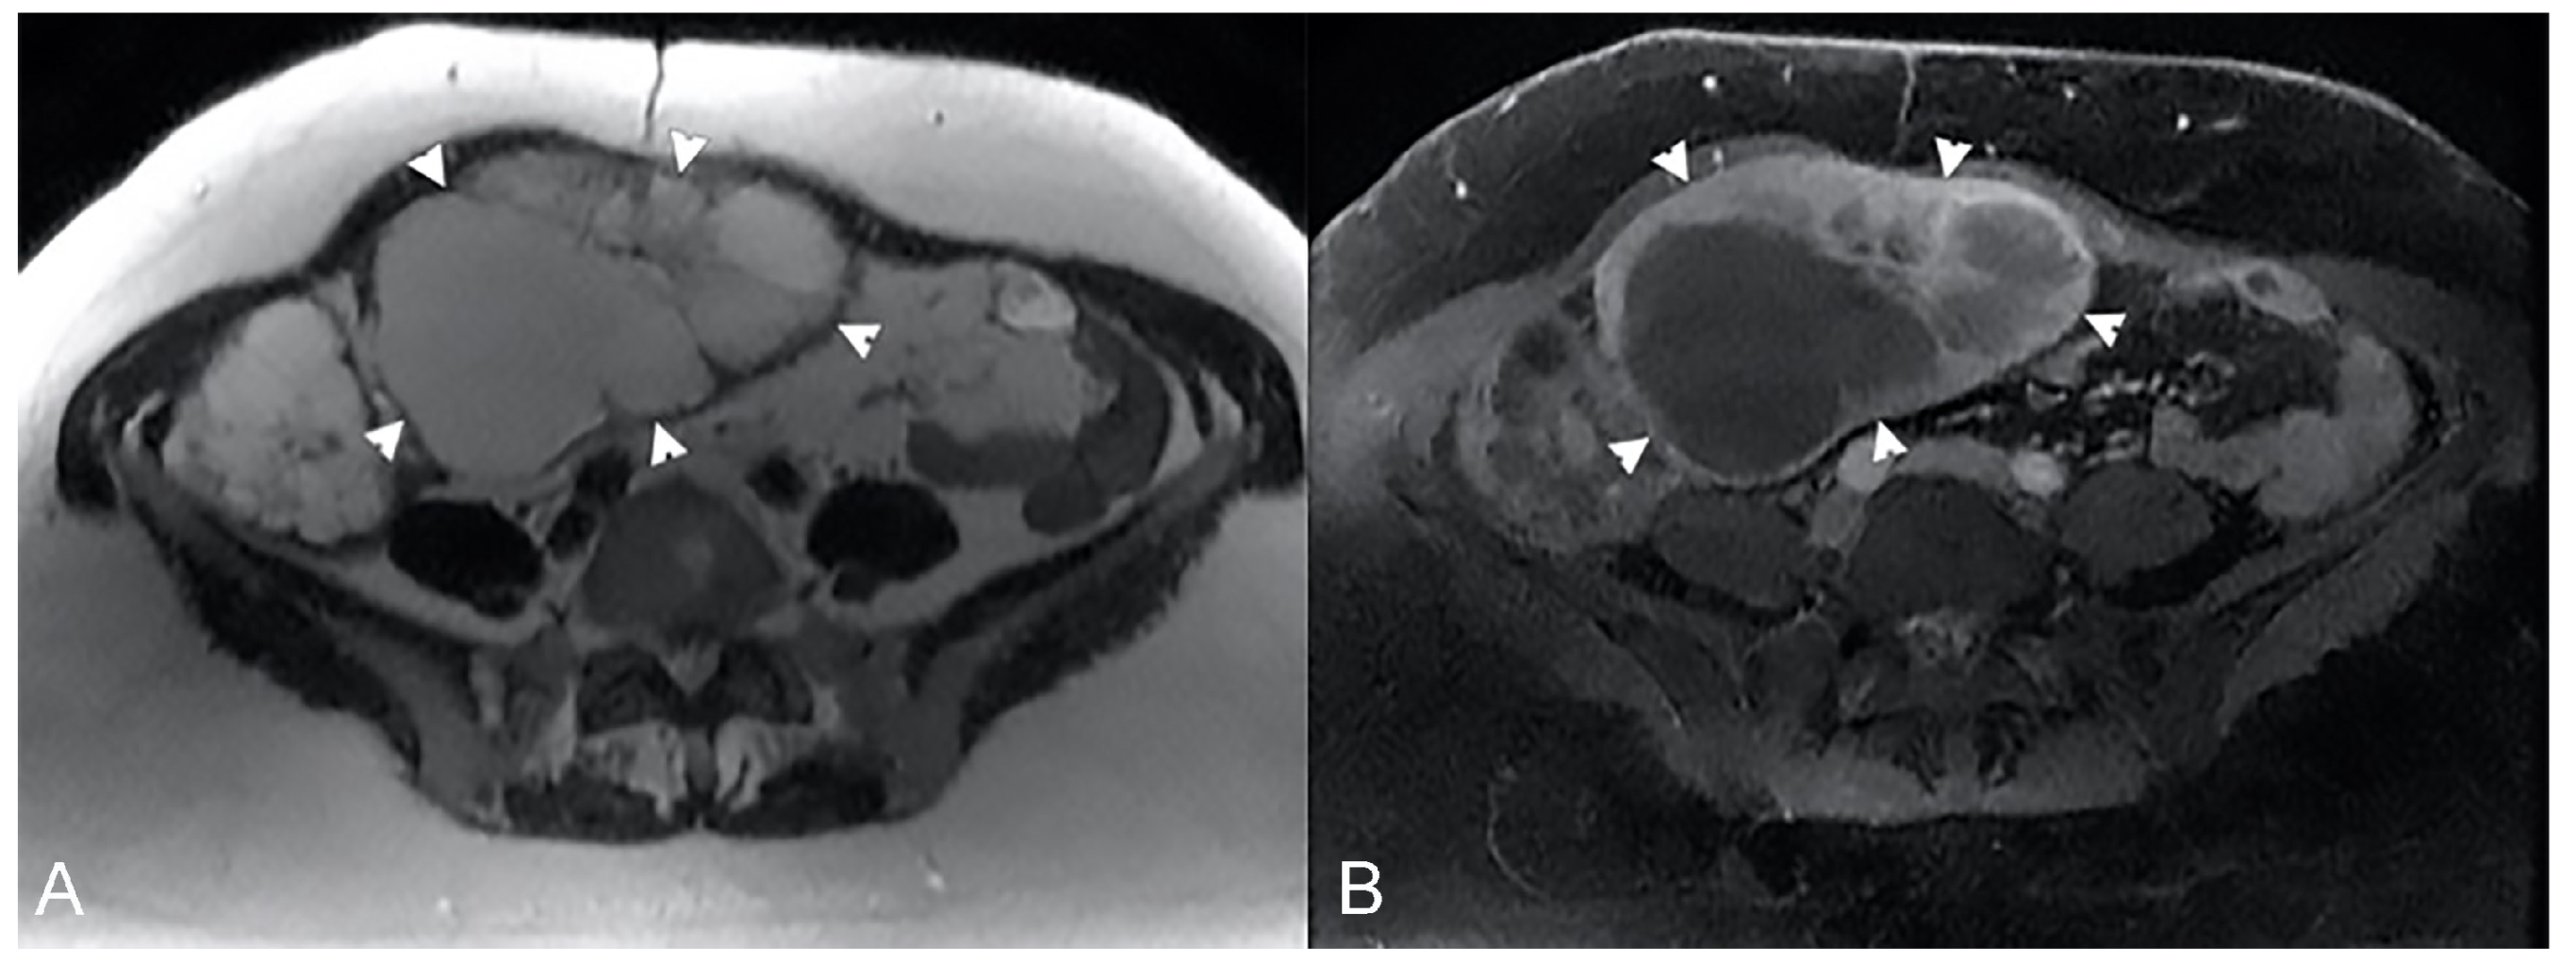

The infiltrative pattern is characterized by circumferential involvement of the wall, and it is responsible for different degrees of wall thickening and disappearing of the normal wall layers. Bowel wall infiltration looks like segmental and circumferential thickening, with homogeneous enhancement after gadolinium injection [33,34] (Figure 22).

Figure 22.

Example of Lymphoma in a 71-year-old male patient (the same patient in Figure 1C). (A) Axial T2-weighted image shows a marked asymmetric thickening of an ileal loop in the pelvis (arrows). (B) An axial T2-weighted image on a different plane shows multiple enlarged mesenteric lymph nodes (arrowheads).